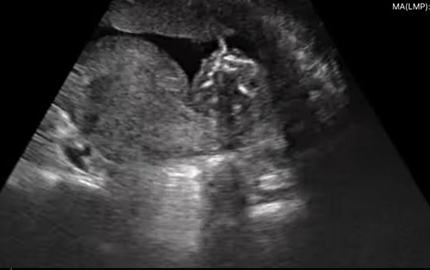

Whole Body Abdomen Ultrasound Fetal B